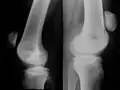

Veraltete Patellafraktur mit massivem Auseinanderweichen der Fragmente. Bild aus einer Arbeit von Hamilton 1875 (aus der voroperativen Zeit), man erkennt auch den vollständigen Funktionsverlust der Kniestrecker.

Die fundamentale Bedeutung der Kniescheibe für den aufrechten Gang macht die Aufmerksamkeit, die ihren Brüchen seit jeher zukommt, verständlich. Aufgrund der oberflächennahen subkutanen Lage der Kniescheibe, der einfach nachvollziehbaren Funktionsabläufe, des erheblichen Funktionsverlustes beim Kniescheibenbruch und aufgrund des hohen Anspruchs, den die Kniescheibenfraktur an den behandelnden Arzt stellt, stand die Patellafraktur schon früh im Mittelpunkt des Interesses von Ärzten und Patienten. Bei der Patellafraktur verliert der Patient nicht nur die Fähigkeit, das Bein aktiv zu strecken, ihm ist es darüber hinaus unmöglich, das Kniegelenk zu stabilisieren, so dass er nicht mehr auf dem verletzten Bein stehen kann. Das klinische Bild der Kniescheibenfraktur mit dem durch die Haut als Delle palpierbaren Frakturspalt, Dislokation und Krepitation (Frakturreiben) wurde bereits von Soranos von Ephesos im ersten Jahrhundert in Rom beschrieben. Die Verunfallten sind entsprechend dem Funktionsverlust hochgradig invalide.